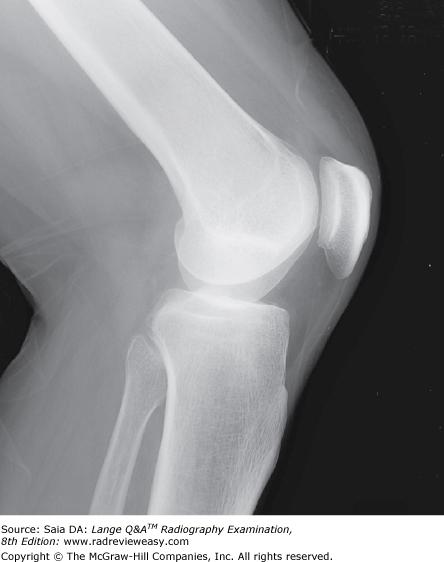

B lateral projection.

-A frontal projection (AP or PA) demonstrates the medial and lateral relationship of structures. A lateral projection demonstrates the anterior and posterior relationship of structures. Two views, at right angles to each other, are generally taken of most structures.